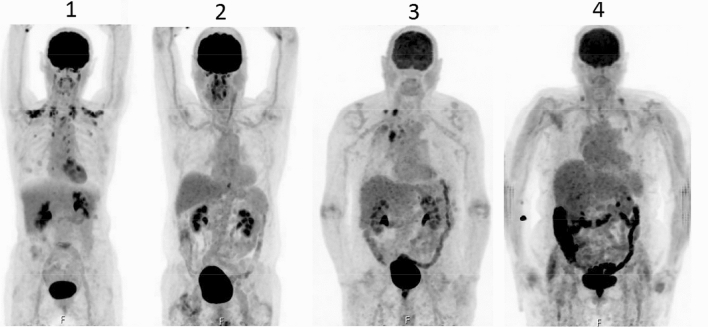

The uptake of FDG also varied between the four segments (Table 2). A high uptake (grade 3–4) in each group was located in the rectosigmoid (100% in the < 48 h group, 76.0% in the ≥ 48 h group, and 21.9% in the control group). Examples of different gradings in four patients are presented in Fig. 1, while the results of the comparison of the different groups are presented below.

Fig. 1.

PET/CT images of four patients with different grades of FDG uptake in the colon, from left to right, corresponding to the four-point scale method of Gontier et al. [2]